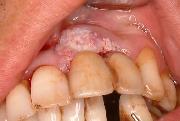

口腔がん

歯肉頬部がん(頬のがん)